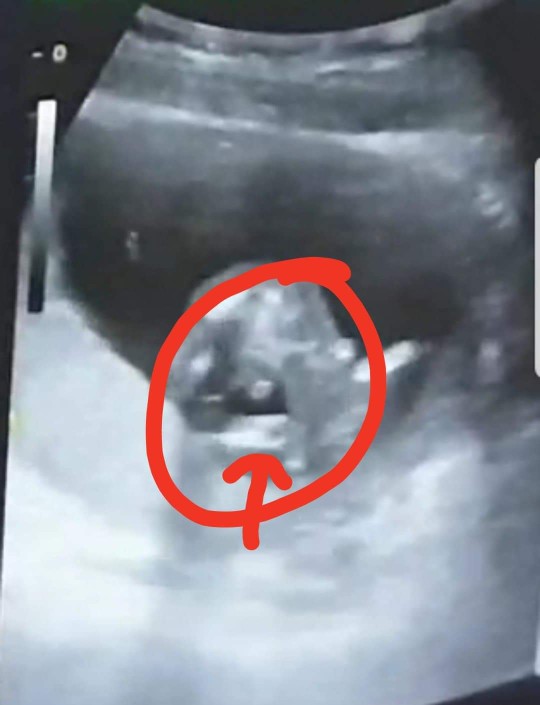

กองก้น โชว์ใข่ชัดมากกค้ะ 14 Week5Day😁💕